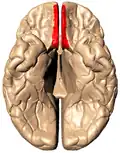

Анимированное изображение, прямая извилина отмечена красным

Базальная поверхность мозга, прямая извилина отмечена красным